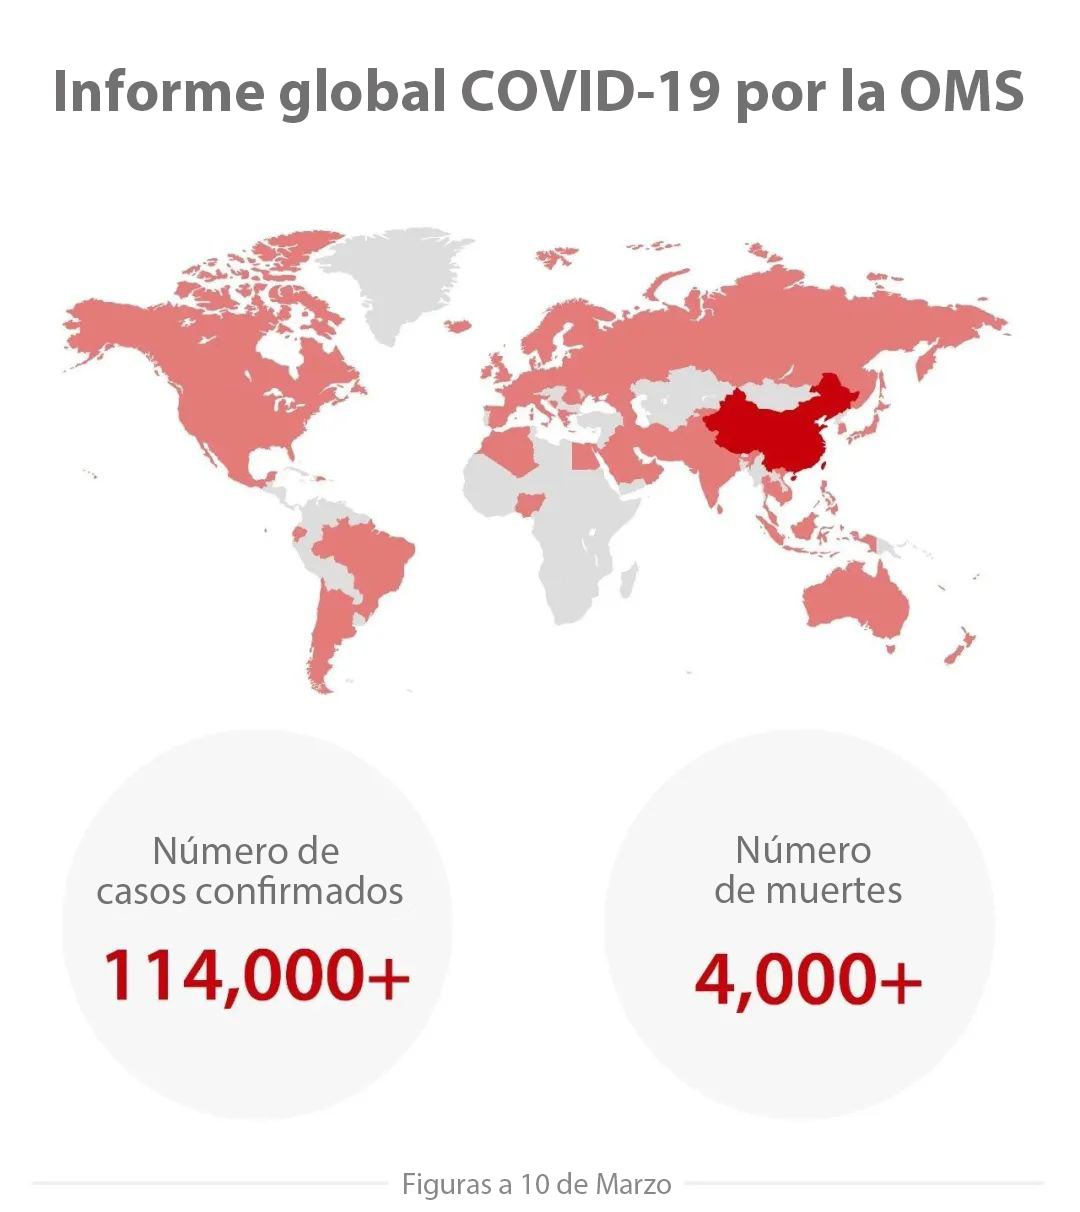

El brote actual de COVID-19, una nueva enfermedad peligrosa por coronavirus causada por el virus SARS-CoV-2, se ha extendido por toda China y otros 114 paĂses y regiones a partir del 10 de marzo. A medida que la epidemia evoluciona rĂĄpidamente, los clĂnicos en todo el mundo trabajan a contrarreloj responder contra el brote.